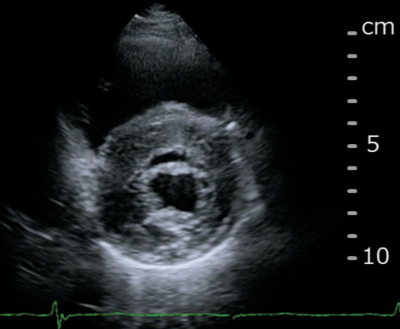

血液所見:赤血球 456 万、Hb 14.5 g/dL、白血球 8,900、血小板 17 万。心エコー図を別に示す。

患者への説明として適切でないのはどれか。

a. 「心臓の壁が厚くなっています」

d. 「心臓の周りに多量の水が溜まっています」